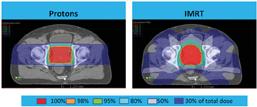

As a new medical center, Hôpital Riviera's daily radiotherapy patient volume started out small, but now the hospital averages 40 patients per day. The introduction of Volumetric Modulated Arc Therapy (VMAT) in many more cases has resulted in a substantial reduction in the time slot — from 15-20 minutes down to 10-15 minutes — which has enabled a 50 percent increase in patients treated per day.